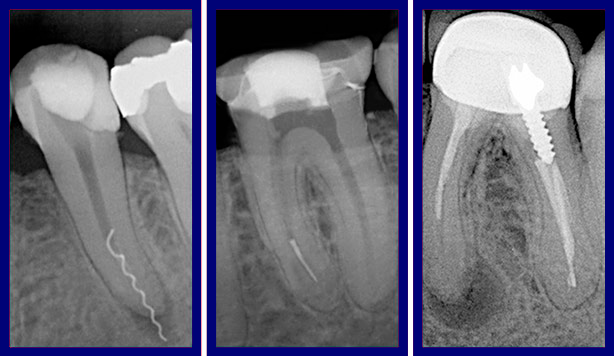

Сложное перелечивание эндодонтически леченного корневого канала: клинические аспекты и современные подходы

Эндодонтическое перелечивание остается одной из наиболее сложных задач в стоматологической практике. Неудачи первичного лечения корневых каналов могут быть связаны с неадекватной механической и медикаментозной обработкой, перфорациями, необнаруженными дополнительными каналами, вертикальными трещинами корня или реинфекцией вследствие негерметичной обтурации. В таких случаях перелечивание требует тщательной диагностики, высокого уровня мастерства врача и применения современных технологий. Показания к перелечиванию 1. Персистирующий или рецидивирующий апикальный периодонтит – подтвержденный рентгенологически или клинически (болезненность при перкуссии, свищевой ход). 2. Неудовлетворительное качество пломбирования каналов (недостаточная длина, поры, выведение материала за апекс). 3. Наличие обломков инструментов, требующих удаления. 4. Перфорации стенок корня или дна полости зуба. 5. Необходимость восстановления коронковой части перед протезированием (например, при наличии штифтов). Диагно

Диагностический алгоритм

2. Рентгенография (прицельный снимок, КЛКТ для оценки 3D-структуры каналов и периапикальных изменений).

Этапы перелечивания

1. Доступ к системе корневых каналов

· Удаление старой реставрации, распломбировка гуттаперчи (с использованием растворителей, файлов или ультразвука).

· Извлечение штифтов (при необходимости – ультразвуковая техника).

2. Прохождение и обработка каналов

· Использование микроскопа для обнаружения дополнительных каналов (MB2 в верхних молярах, медиально-щелевых в нижних).

· Никель-титановые ротационные инструменты (для безопасного прохождения искривленных каналов).

· Ирригация (гипохлорит натрия 3–5%, ЭДТА, ультразвуковая активация).

4. Окончательная обтурация

· Термопластифицированная гуттаперча (система непрерывной волны).

· Биокерамические силеры (повышают герметичность).

Современные методы перелечивания корневых каналов позволяют достичь успеха в 70–85% случаев. Ключевыми факторами являются точная диагностика, использование микроскопа и ротационных систем, а также грамотная медикаментозная обработка. В сложных случаях (вертикальные переломы, значительные перфорации) может потребоваться сотрудничество с хирургом-стоматологом для проведения резекции верхушки корня или удаления зуба с последующей имплантацией.